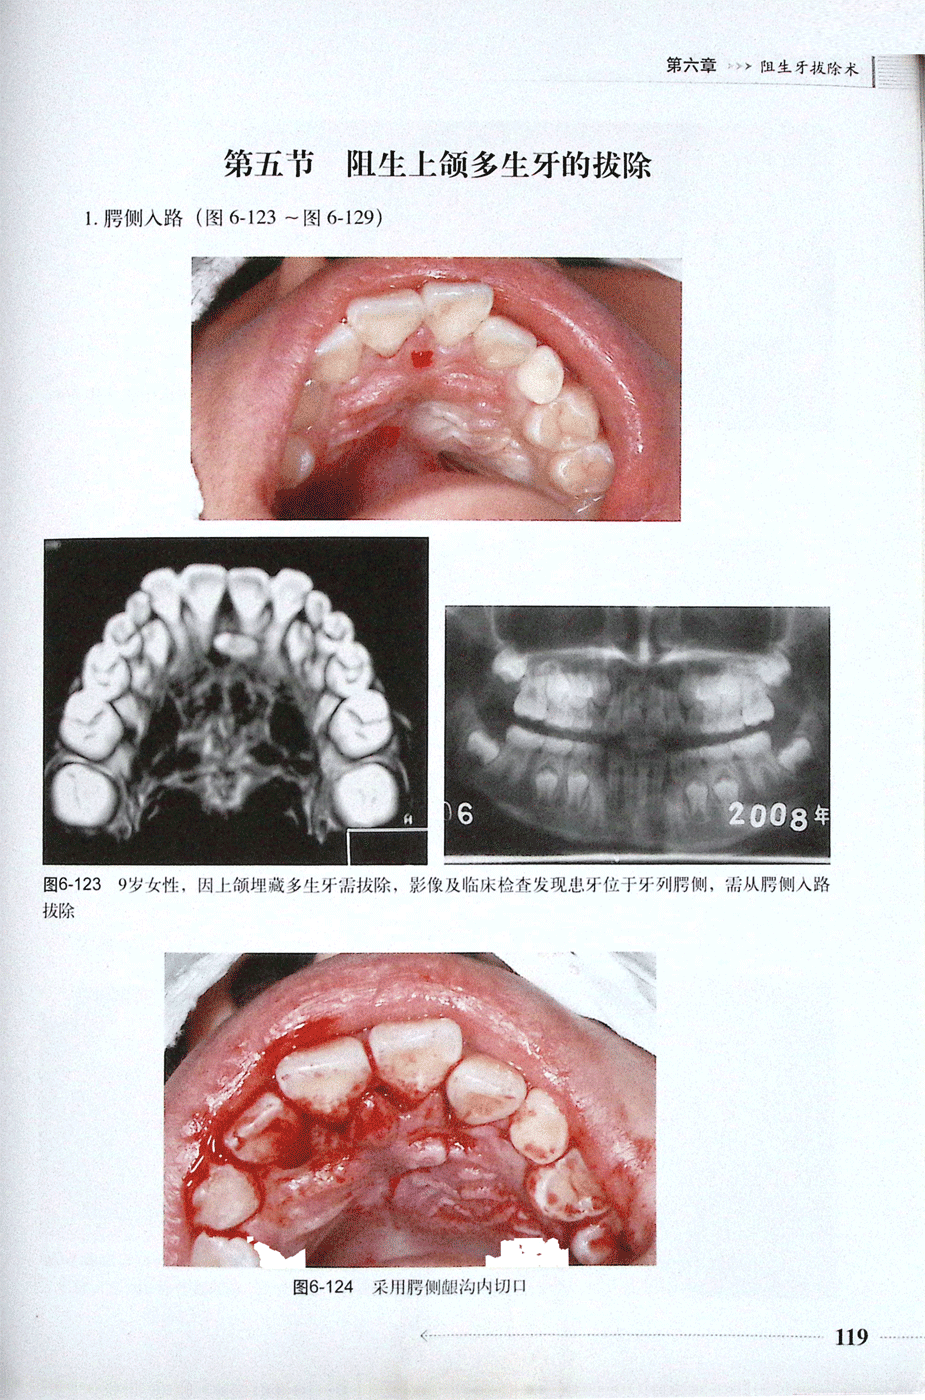

第五节、阻生上颌多生牙的拔除(一)